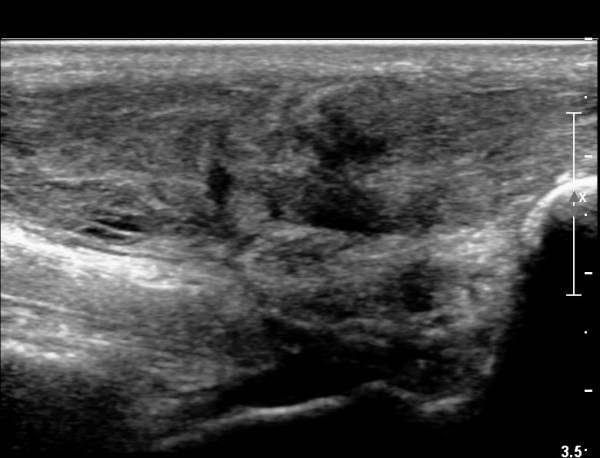

³»Ãø ºñº¹±Ù Á¾´Ü¸é°Ë»ç¿¡¼­ ³»Ãø ¹èº¹±Ù ¸»´ÜºÎ ÆÄ¿­°ú °¡Àڹ̱٠½ÉºÎ¿¡ ¼ö¾×Àú·ù°¡ °üÂûµÊ(»çÁø 1, 2).

¾ÆÅ³·¹½º°Ç Á¾´Ü¸é°Ë»ç¿¡¼­ ¾ÆÅ³·¹½º°Ç ¸»´ÜºÎ¿¡ ¾ÆÅ³·¹½º°ÇÀÇ Àú¿¡ÄÚºÎÁ¾, ±¹¼ÒÀû ¿¬°á¼º ¼Ò½Ç,

¹ß¸ñ°üÀý ÈĹæºÎ¿¡ ¼ö¾×Àú·ù°¡ °üÂûµÊ(»çÁø 3, 4, 5).